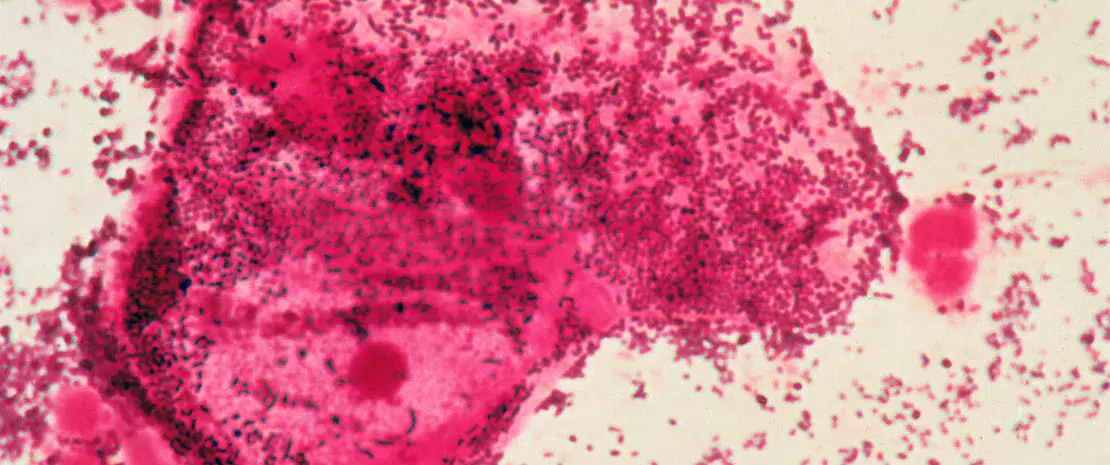

La (sidenote: Vaginose bactérienne La vaginose bactérienne (VB) est un type d'inflammation vaginale causée par un déséquilibre des espèces de bactéries qui sont normalement présentes dans le vagin. ) (VB) est souvent un signe caractéristique d'un déséquilibre dans le microbiote vaginal, une maladie qui pourrait résulter de la transmission sexuelle de bactéries. Bien que la communauté scientifique reconnaisse l'éventualité d'une telle transmission, la compréhension définitive nous échappe encore. Des chercheurs américains de l'University of Maryland School of Medicine ont étudié comment des souches bactériennes similaires se comportaient entre des partenaires sexuels et au sein de réseaux sexuels plus vastes, afin de mieux comprendre la transmission sexuelle et d'améliorer la prise en charge de la maladie pour les deux partenaires. 1

Les chercheurs ont recueilli et analysé des échantillons de prélèvements vaginaux et péniens à l'aide du séquençage métagénomique global, une méthode permettant de lire l'intégralité des séquences ADN présentes dans un échantillon, afin d'analyser en détail la communauté microbienne. Ils ont utilisé des outils comme inStrain pour évaluer la « concordance des souches », ou le degré de similitudes génétiques, entre les bactéries trouvées chez différents individus, en vue d'identifier si les souches sont partagées par contact sexuel.

Sur 54 participants, l'étude a identifié 115 cas de recoupements de souches bactériennes parmi 25 espèces. Étonnamment, Lactobacillus iners a été transmis chez 6 % des participantes, ce qui suggère des voies de transmission directe lors d'interactions entre personnes de même sexe. Des comparaisons directes ont révélé un taux de partage de souches bactériennes bien supérieur en cas de contacts sexuels par rapport à l'absence de contact.